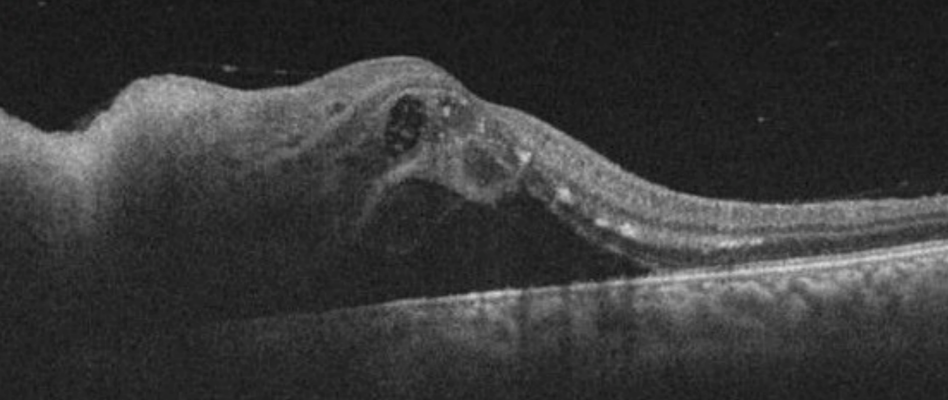

Figure 4: A serous macular detachment

After the initiation of treatment, the optic disc edema, focal retinal infiltrates, retinal haemorrhage, serous retinal detachment, and macular exudates gradually decreased (Figure 6 [Fig. 6]). The cells in the anterior chamber and vitreous resolved over the treatment course. However, it is noteworthy that the focal retinitis persisted and doxycycline was prescribed for 3 months. Six months after the start of treatment, macular atrophy developed and the visual acuity remained 20/40.

Figure 6: After the treatment, optic disc edema, focal retinal infiltrates, retinal haemorrhage, serous retinal detachment, and macular exudates decreased.